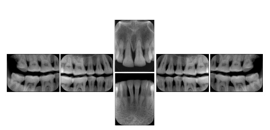

In most standard cases, images are oriented in structured layouts. These structured displays are useful to be shared between providers for reference purposes.

Table OO.1.1-1 shows structured display standard templates, where Viewset ID is based on the Japanese Society for Oral and Maxillofacial Radiology (JSOMR) classification provided by JIRA (Japan Medical Imaging and Radiological Systems Industries Association, www.jira-net.or.jp). Expected or typical teeth to be imaged location, region and designation codes are based on ISO 3950-2010, Dentistry - Designation system for teeth and areas of the oral cavity. For all the hanging protocols listed in OO.1.1-1, the value to use for Hanging Protocol Creator (0072,0008) is "JSOMR" and the value to use for Hanging Protocol Name (0072,0002) does not include "JSOMR" (e.g., "DL-S001A", not "JSOMR DL-S001A").

Table OO.1.1-1. Hanging Protocol Names for Dental Image Layout based on JSOMR classification